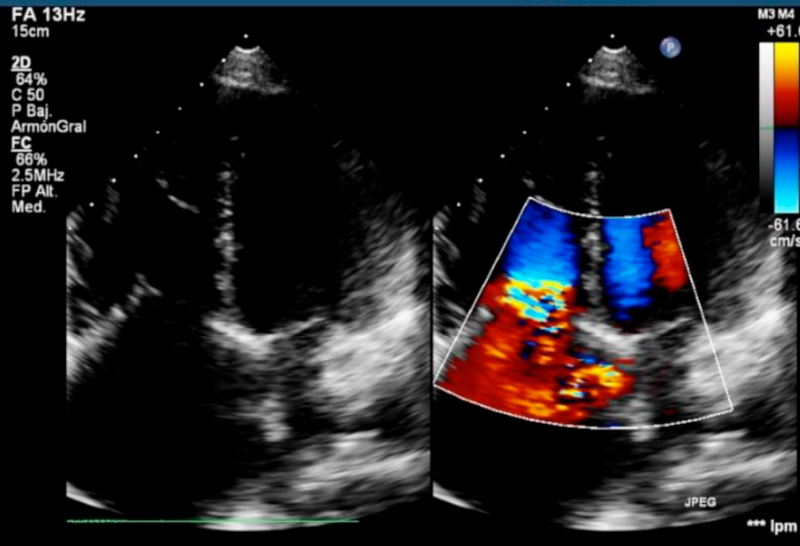

En el ecocardiograma transtorácico: ventrículo izquierdo de dimensiones conservadas, con fracción de eyección 76%, movimiento paradojal del septum interventricular, septum interauricular intacto con relación QP/QS normal; aurícula izquierda de dimensiones conservadas, aurícula derecha dilatada, con presión de 20 mm Hg, ventrículo derecho dilatado con diámetro diastólico de 44 mm y función sistólica normal. Se verifica insuficiencia mitral leve, aparato valvular tricuspídeo hiperecogénico y apertura valvular fija en todo ciclo cardíaco, insuficiencia tricuspídea grave, aumento de la velocidad anterógrada y presión sistólica de la arteria pulmonar estimada de 28 mm Hg.Tronco y ramas pulmonares conservados, insuficiencia pulmonar grave con flujo reverso en ramos pulmonares. Ausencia de masas intracavitarias (Figura 2).